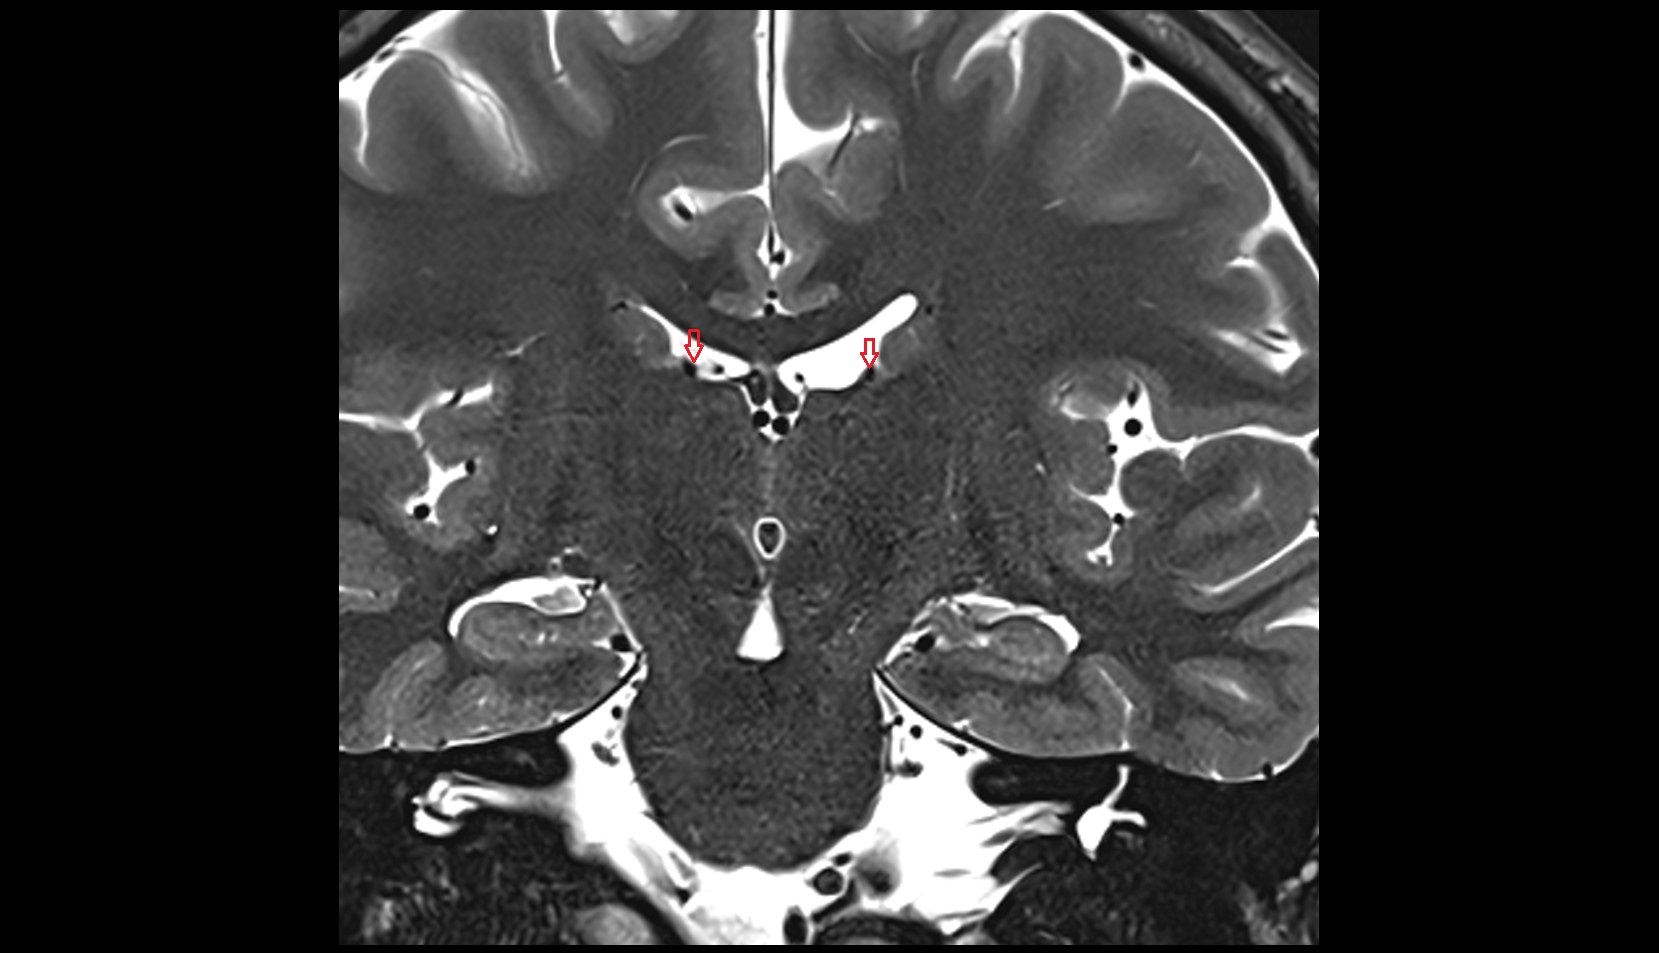

- Fetal brain

- Fetal caudate nucleus

- Fetal thalamus

- Fetal lateral ventricle